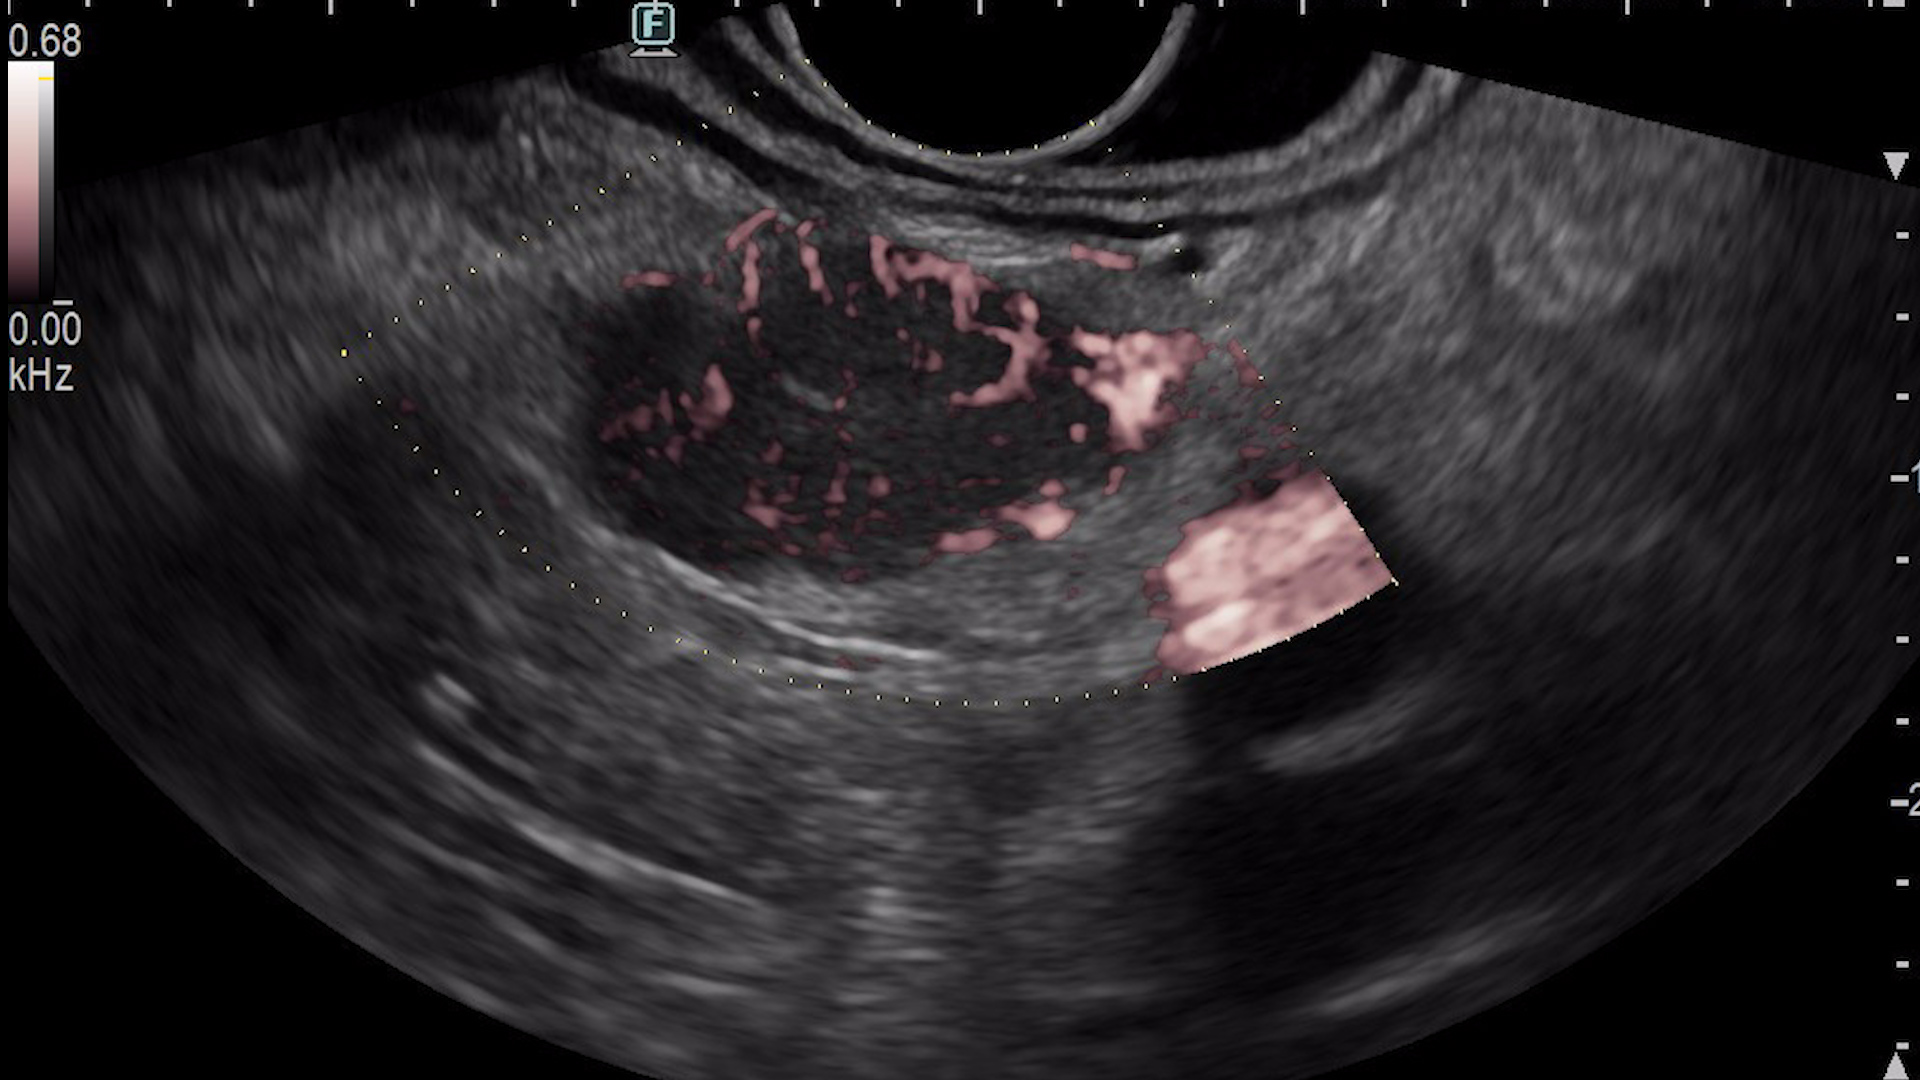

Consequently, an endoscopic ultrasound examination was carried out with tissue acquisition from the mass using a 22G Franssen-type needle (Acquire, Boston Scientific). The tumor was hypervascular on both color Doppler (Fig. 3a), detective flow imaging (Fig. 3b) and contrast-enhanced harmonic imaging (CHI) endoscopic ultrasound (Fig. 4). Histopathology was conclusive for a well-differentiated G1 neuroendocrine tumor, while immunohistochemistry confirmed the diagnosis, showing a Ki 67 index of 1%.